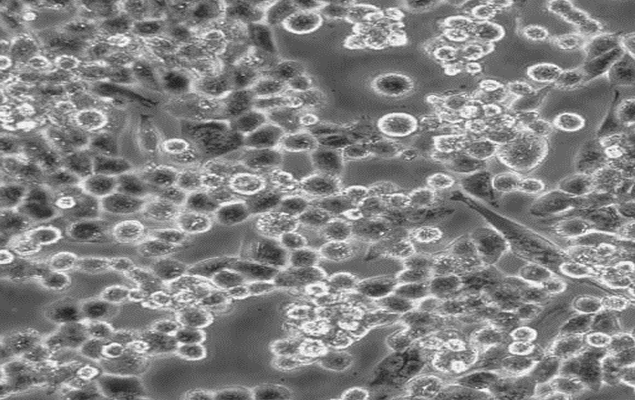

MDA-MB-231-luc;人乳腺癌细胞-荧光素酶标记